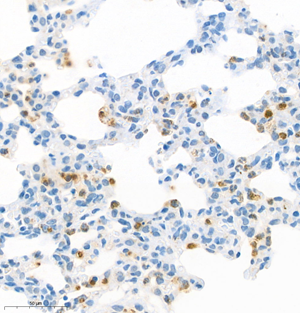

| IHC analysis of mpo (GB11224). Sample: Rat lung+lps (Paraffin), 4% PFA (G1101) 12-24h. Antigen retrieval: Citrate buffer (pH 6.0) (G1201),98°C,20 min. Blocking buffer: 3% BSA in PBS (GC305010), RT, 30min. Primary antibody: 1: 1200, 4°C overnight. Secondary antibody: HRP Goat Anti-Rabbit lgG (GB23303), 1: 200 RT 1h. |